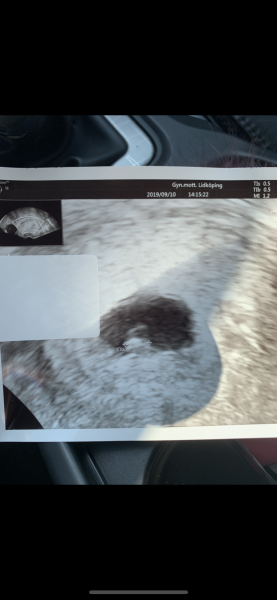

Inväntar ultraljud nu för att se vad mina bruna flytningar innebär.. har ställt in mig på missfall dock :-/ så nervös just nu.. denna bergodalbanan alltså

Allt såg jätte bra med bebis

Vecka 6+2

Kändes helt sjukt att se det lilla hjärtat slå.. var ju såååå inställd på att det skulle vara tomt

så det vart helt fantastiskt <3

Hade brunt på bim och och sen inget fören nu 2 veckor senare.. hon kunde inte alls se vart det kom ifrån då det inte var något nu.. Men pga flera missfall och flera prematurer ska vi följas noga och ofta och även äta trombyl fram till v 36 och progesteron kräm fram till vecka 22.. Ska även få göra kub denna graviditet fast jag är under 35 år